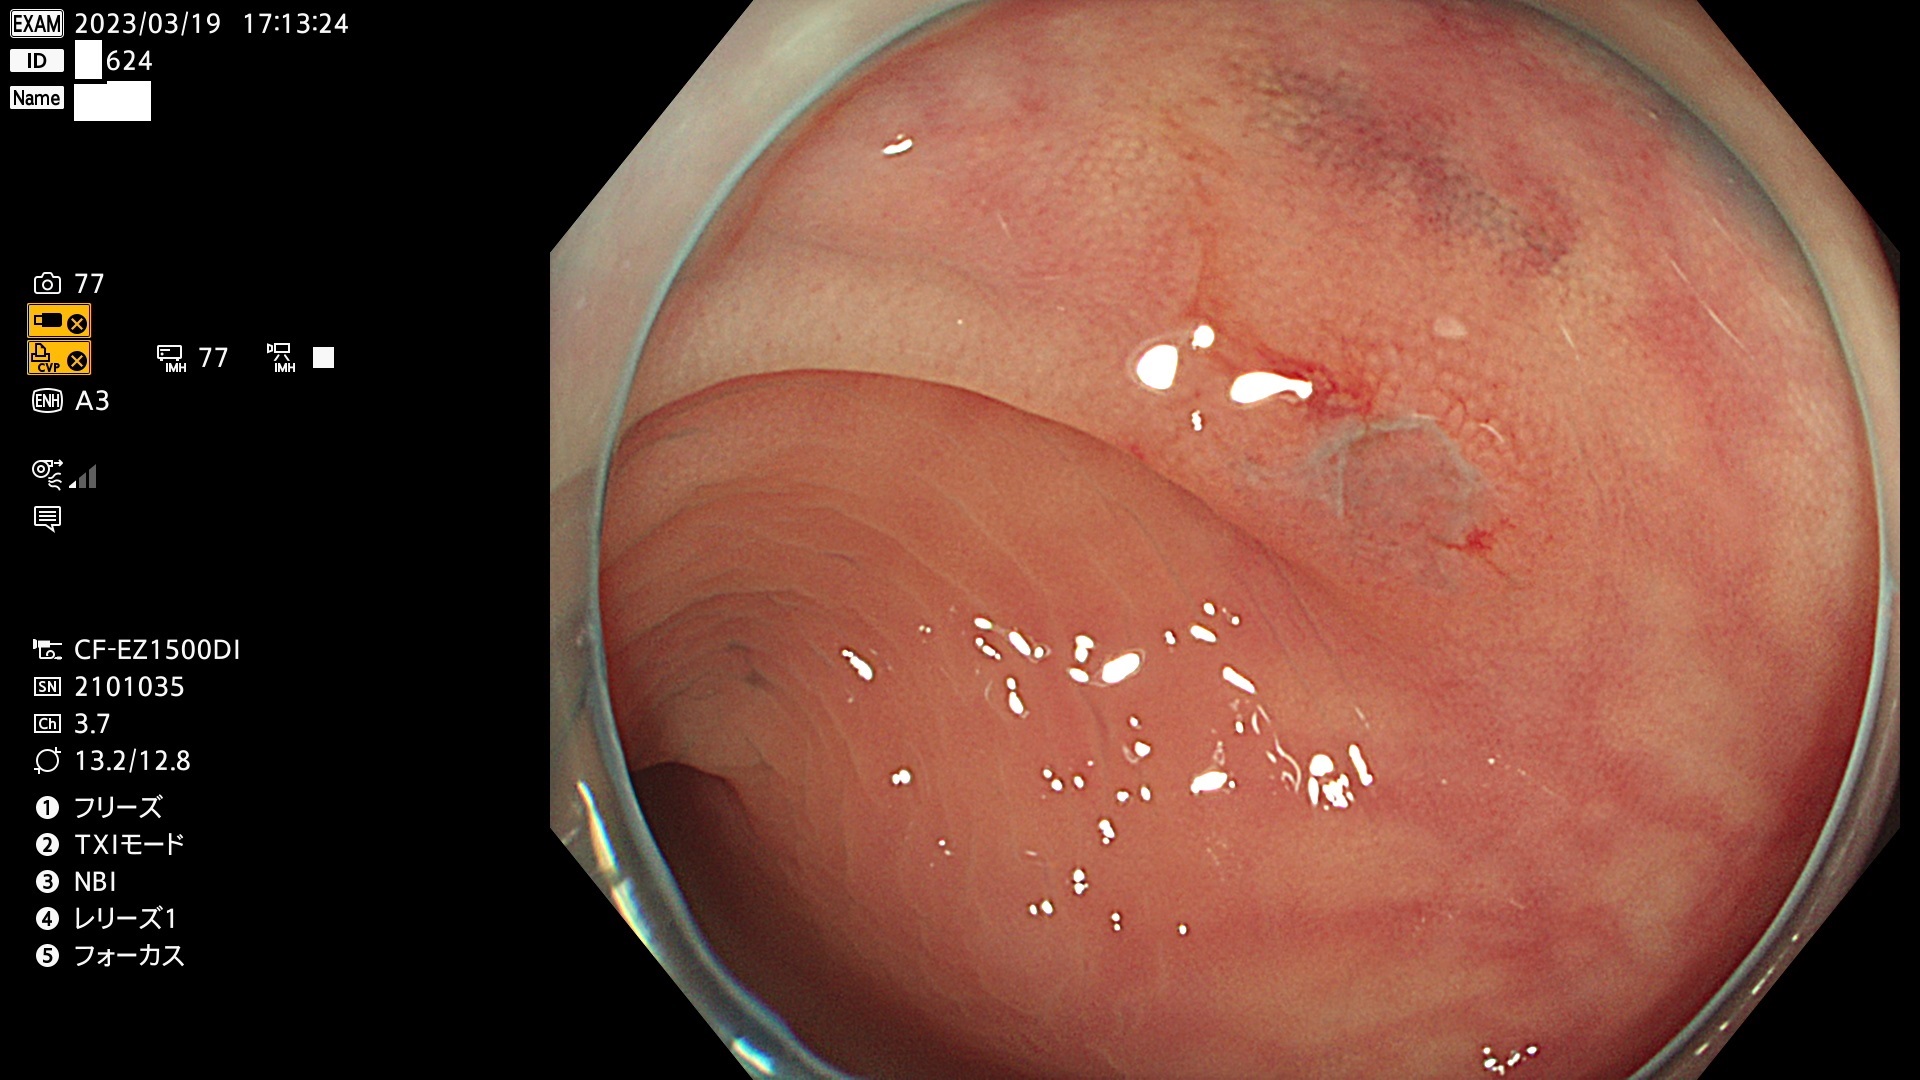

ビランと紛らわしいUc型腺腫(最も危険な前癌病変)

以下は当院で経験した「ビランと鑑別の難しいUc型腺腫」です(全て、病理で腺腫を確認済み)。

このような病変は表面を拡大観察しても診断は不可能であり、現在の内視鏡診断の「限界を超えた病変」と言えます。現実的な対策は「典型的なビランと異なる」と感じたら、「コールド法で積極的に切除する」ことと考えます。もちろん「結局はビランだった(不要な過剰切除だった)」ということもあります。しかしコールド法なら重篤な合併症は稀であり、医師は切除を躊躇すべきではないと考えます。